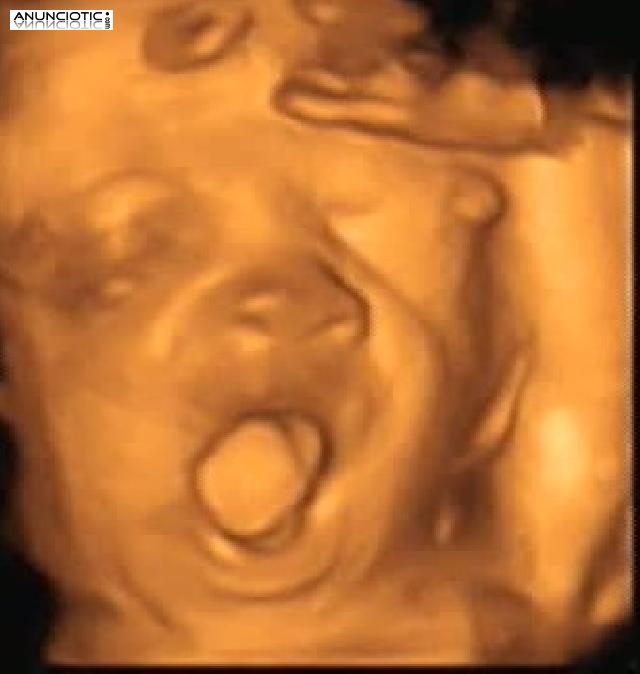

Ecomamá es un centro de imagen 4d prenatal cuyo objetivo es dar a conocer al bebé antes de su nacimiento. Esta maravillosa experiencia permite adentrarnos al pequeño mundo en el que vive el bebé. Gracias a ello se pueden ver gestos faciales nunca vistos como el bostezo, una sonrisa, el parpadeo o la succión. Todo ello en un ambiente cálido relajado y con todas las comodidades.

Un regalo para tu bebé a través de nuestra tecnología 4d prenatal.